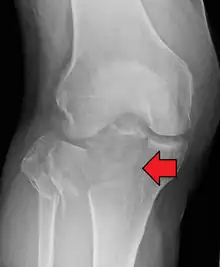

Fractures of the tibial plateau are caused by a varus (inwardly angulating) or valgus (outwardly angulating) force combined with axial loading or weight bearing on knee. The classically described situation in which this occurs is from a car striking a pedestrian's fixed knee (bumper fracture). A bumper fracture is usually a fracture of the lateral tibial plateau, caused by a forced valgus movement. This causes the lateral part of the distal femur and the lateral tibial plateau to come into contact, compressing the tibial plateau and causing the tibia to fracture. The name of the injury is because it was described as being caused by the impact of a car bumper on the lateral side of the knee while the foot is planted on the ground, although this mechanism is only seen in about 25% of tibial plateau fractures.[5] The term "bumper fracture" was coined in 1929 by Cotton and Berg.[6] Fracture of the neck of the fibula may also be found, and associated injury to the medial collateral ligament or cruciate ligaments occurs in about 10% of cases.[7][8]

However, most of these fractures occur from motor vehicle accidents or falls. Injury can be due to a fall from height in which knee forced into valgus or varus. The tibial condyle is crushed or split by the opposing femoral condyle, which remains intact. The knee anatomy provides insight into predicting why certain fracture patterns occur more often than others. The medial plateau is larger and significantly stronger than the lateral plateau. Also, there is a natural valgus or outward angulation alignment to the limb which coupled with the often valgus or outwardly angulating force on impact will injure the lateral side. This explains how 60% of plateau fractures involve the lateral plateau, 15% medial plateau, 25% bicondylar lesions. Partial or complete ligamentous ruptures occur in 15-45%, meniscal lesions in about 5-37% of all tibial plateau fractures.[9]